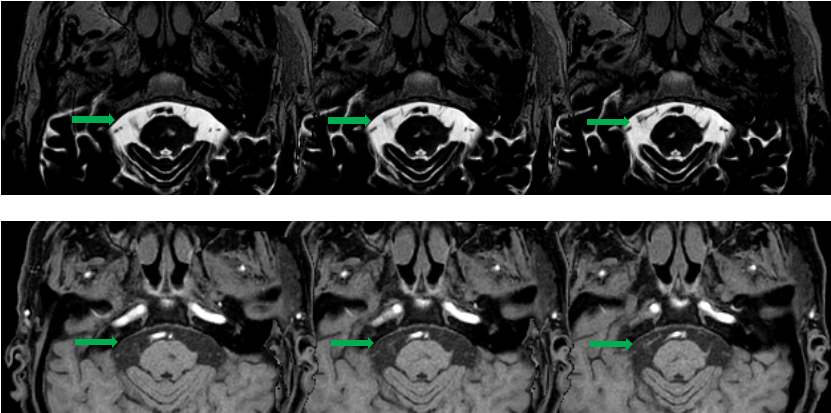

MRI提示患者右侧三叉神经与小脑上动脉(绿色箭头)关系密切